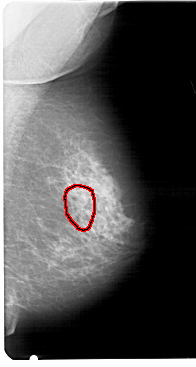

FILE: A_1458_1.RIGHT_MLO.OVERLAY

TOTAL_ABNORMALITIES 1

ABNORMALITY 1

LESION_TYPE CALCIFICATION TYPE PLEOMORPHIC DISTRIBUTION CLUSTERED

ASSESSMENT 4

SUBTLETY 3

PATHOLOGY BENIGN

TOTAL_OUTLINES 1

BOUNDARY

FILE: A_1458_1.RIGHT_CC.OVERLAY